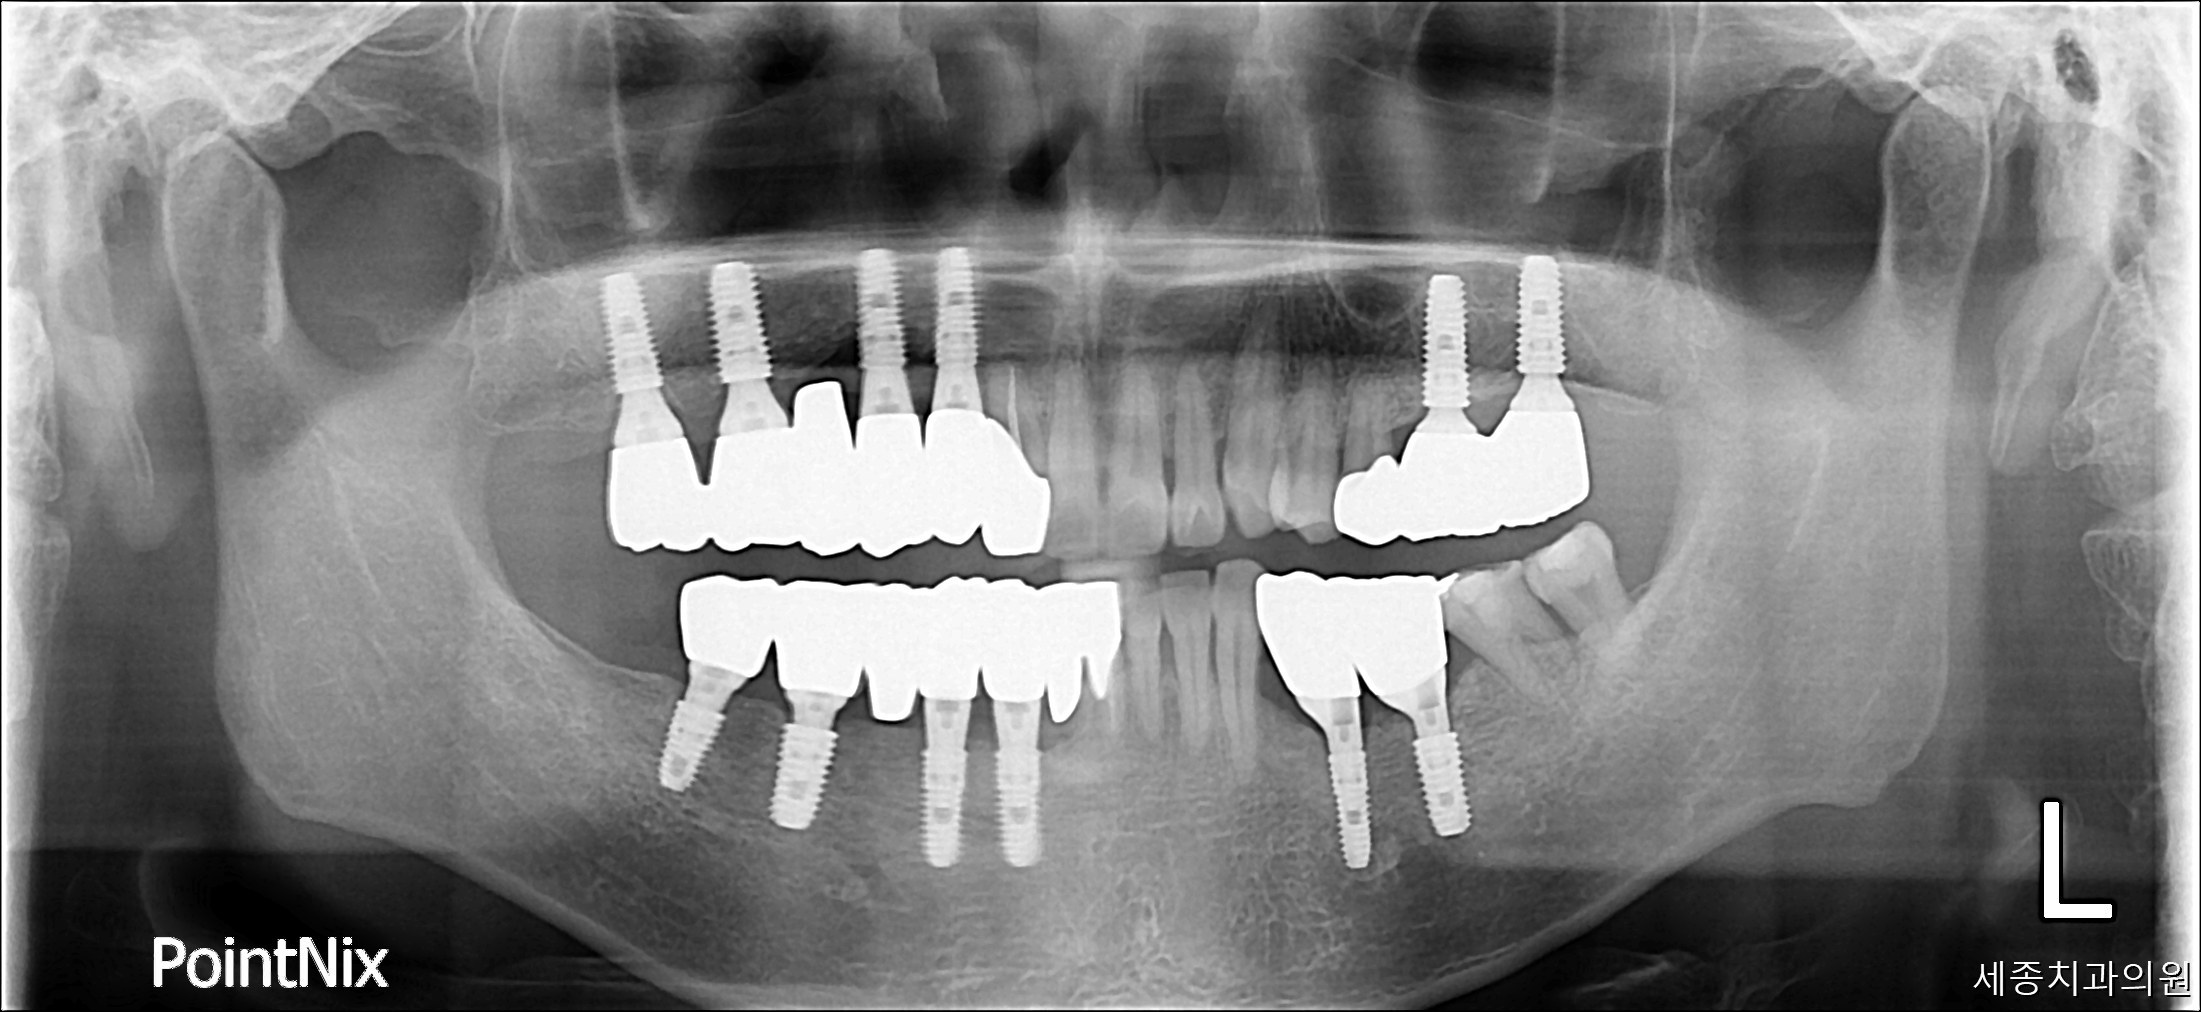

최현일_후.jpg

치료후 : 2017-10-27